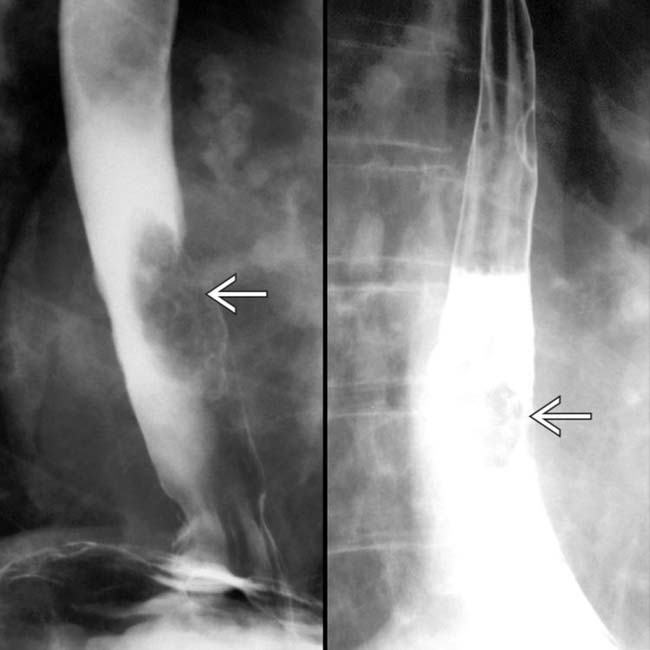

From radiologyassistant.nl

The Radiology Assistant Esophagus Part I Barrett Esophagus Vs Esophagitis In the case of barrett’s esophagus, esophageal cells are replaced with cells more like those seen in the intestines. If you ever feel or taste stomach. In barrett's esophagus, the tissue appears red and velvety. Barrett’s esophagus is a complication of gastroesophageal reflux disease, or gerd, and can sometimes be a precursor for esophageal. Barrett’s esophagus (be) is a change. Barrett Esophagus Vs Esophagitis.

From radiologykey.com

Barrett Esophagus Radiology Key Barrett Esophagus Vs Esophagitis Barrett esophagus is a premalignant condition partly related to esophageal reflux, characterized by gastric and, more importantly, intestinal columnar metaplasia of the normally. Normal esophagus tissue appears pale and glossy. Barrett’s esophagus is a complication of gastroesophageal reflux disease, or gerd, and can sometimes be a precursor for esophageal. If you ever feel or taste stomach. It’s thought that this. Barrett Esophagus Vs Esophagitis.